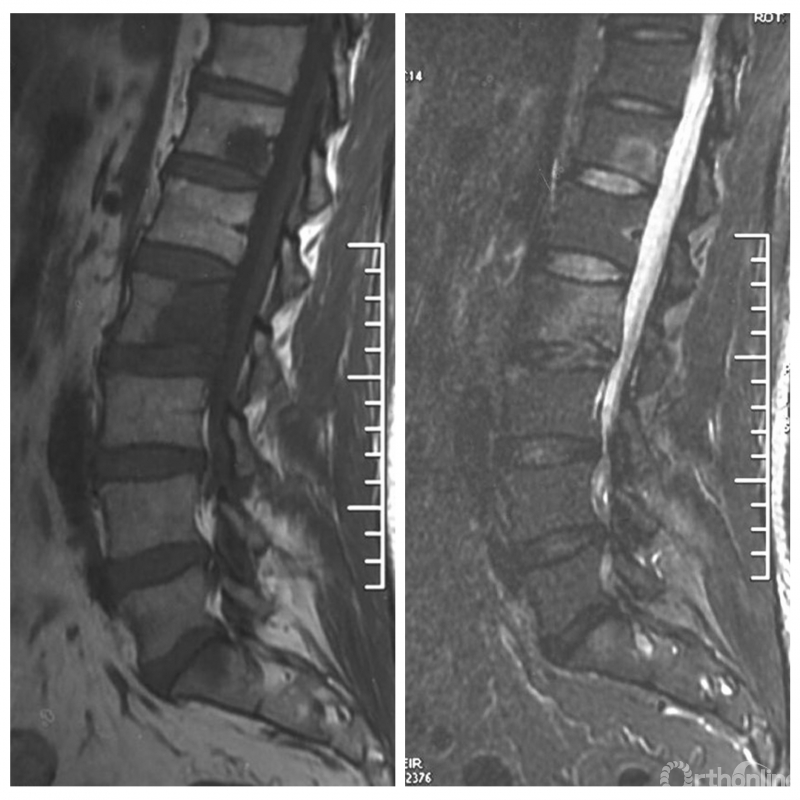

影像学资料

PVP治疗

术后6个月

入院影像学资料